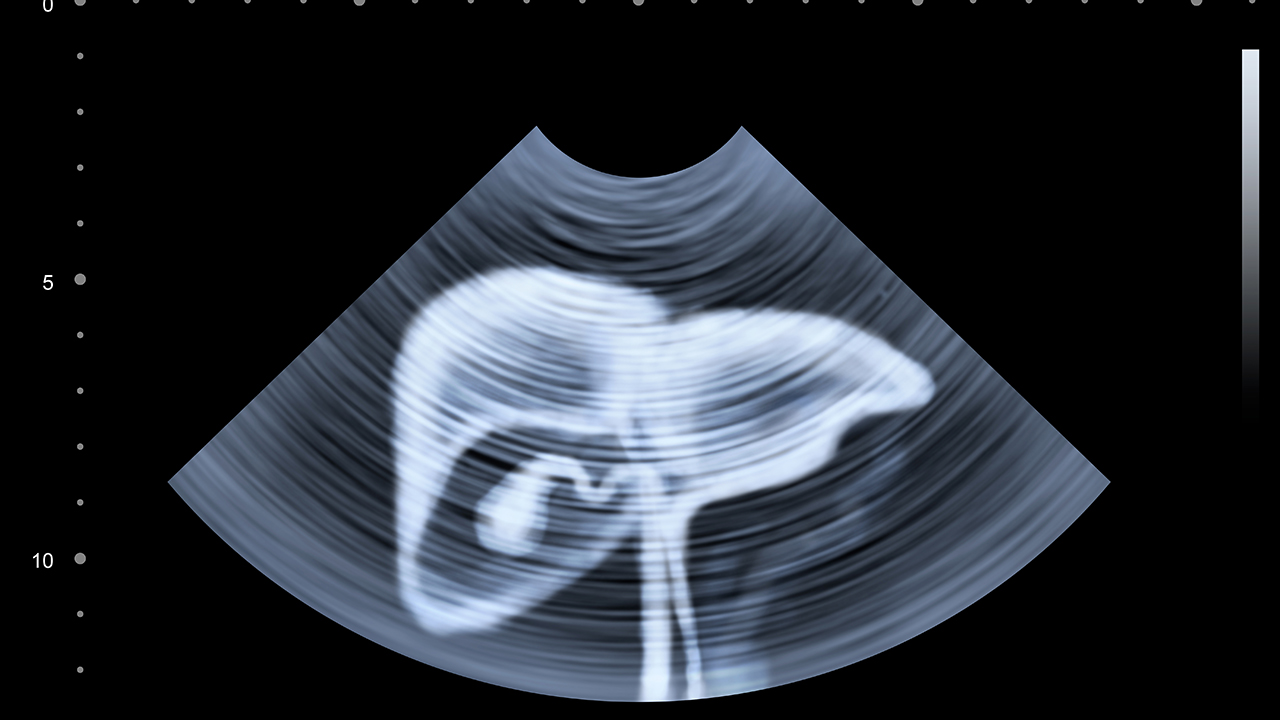

肝癌预防需要从日常生活做起,保持健康的生活方式至关重要。建议避免过量饮酒,注意饮食卫生,避免食用霉变食物。慢性肝炎患者应定期复查,遵医嘱治疗。接种乙肝疫苗是预防肝癌的有效措施。保持规律作息,适当运动,增强体质,有助于降低肝癌发病风险。对于高危人群,建议每6-12个月进行一次肝脏超声和甲胎蛋白检查,做到早发现、早治疗。